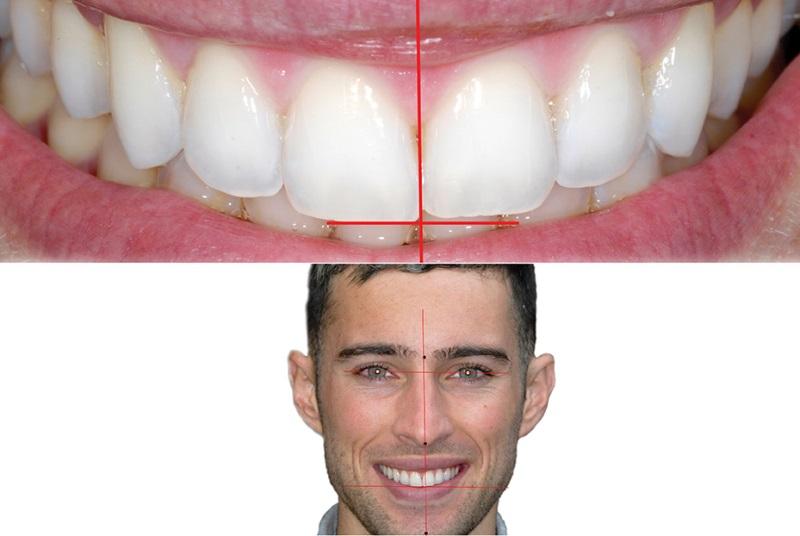

Улыбки в фотографиях: типы и комической моменты

Раздел: Фотогалерея мыслей